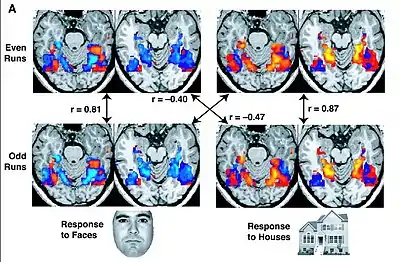

The GLM model does not take into account the contribution of relationships between multiple voxels. Whereas GLM analysis methods assess whether a voxel or region's signal amplitude is higher or lower for one condition than another, newer statistical models such as multi-voxel pattern analysis (MVPA), utilize the unique contributions of multiple voxels within a voxel-population. In a typical implementation, a classifier or more basic algorithm is trained to distinguish trials for different conditions within a subset of the data. The trained model is then tested by predicting the conditions of the remaining (independent) data. This approach is most typically achieved by training and testing on different scanner sessions or runs. If the classifier is linear, then the training model is a set of weights used to scale the value in each voxel before summing them to generate a single number that determines the condition for each testing set trial. More information on training and testing classifiers is at statistical classification.[62] MVPA allows for inferences about the information content of the underlying neural representations reflected in the BOLD signal,[63] though there is a controversy about whether information detected by this method reflects information encoded at the level of columns, or higher spatial scales.[64] Moreover, its harder to decode information from the prefrontal cortex compared to visual cortex and such differences in sensitivity across regions makes comparisons across regions problematic.[65] Another method used the same fMRI dataset for visual object recognition in the human brain is depending on multi-voxel pattern analysis (fMRI voxels) and multi-view learning which is described in,[66] this method used meta-heuristic search and mutual information to eliminate noisy voxels and select the significant BOLD signals.